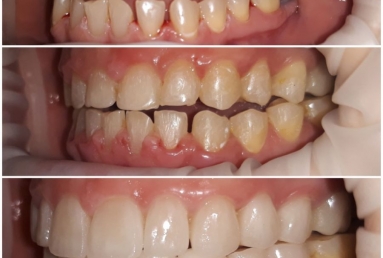

orthodontic treatment, full ceramic crowns

Our patient had general dental abrasion due to maloclusion. After orthodontic treatment, the upper teeth received full ceramic crowns, while the lower were restored with crowns and veneers.

We managed to solve partialy the orthodontic problem and at the same time restore the frontal teeth with esthetic ceramics for a perfect smile.